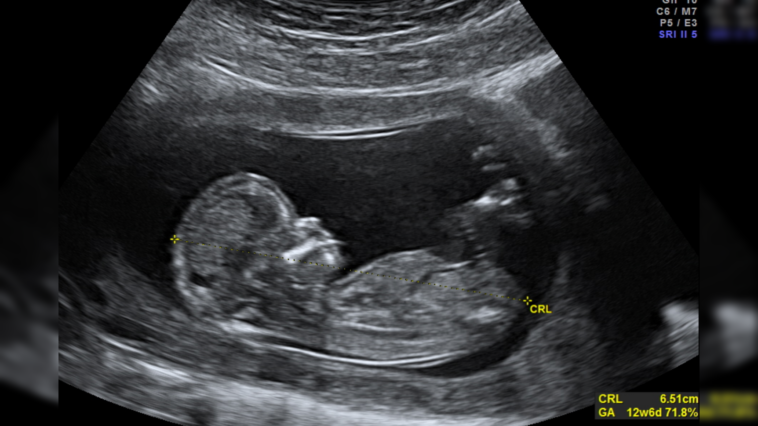

Wikicommons/Photo by Wolfgang Moroder